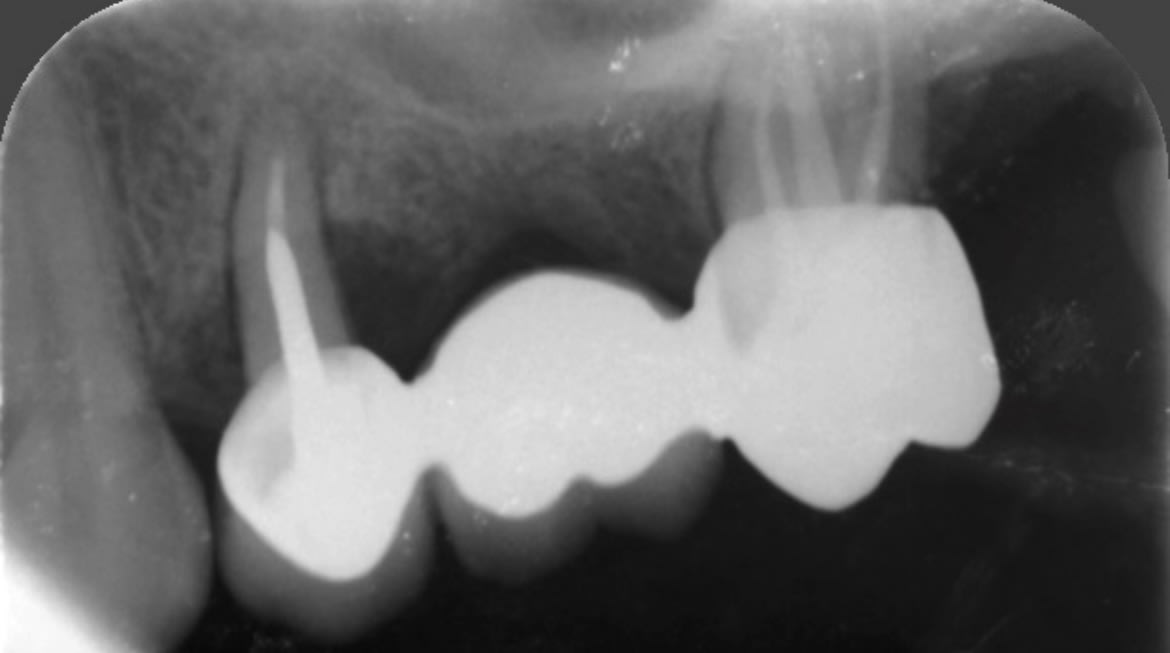

Quelle est la cause principale de l’image sur la prémolaire ?

Et surtout quelle est la cause secondaire qui a engendré cela ?

Malgré la misérable qualité de l'image on voit le trait de fracture en regard le l'extrémité du tenon.

enlaye: j'avais écrit que le trait à l'extrémité du tenon sur la racine, se poursuit en mésial et en distal et marque pour moi une différence de densité osseuse.

Par contre en regardant bien la radio, quelque mm au dessus il semble y avoir, un trait de fracture et là uniquement sur la racine.

Si! Il y a une fêlure . Et elle a mal. Ça c’est certain. La question est pourquoi mange t elle que de ce côté alors qu’elle a des dents de l’autre côté et qu’elle n’a pas de problème majeur niveau occlusion ?

Donc t’as répondu à la question : cause principale = fêlure (et le trait ne peut pas se voir à la radio, contrairement à fracture). Cause secondaire : sur sollicitation du bridge, donc usure accélérée (en gros la cause c’est la vieillerie)

Heureusement qu’il est là Vulpi. Elle a une hemiagueusie (ça compte triple au scrable) , et une paralysie faciale. En gros elle s’est fait opérer d’un chondrosarcome au niveau du crâne. Et suite à l’opération, elle a eu une perte de goût que d’un côté. Donc logiquement elle balade le bol alimentaire que d’un côté pour avoir le goût . Pareil si elle mange du mauvais côté, elle fait des fausses routes. Du coup elle mange que du côté où on trouve le bridge.